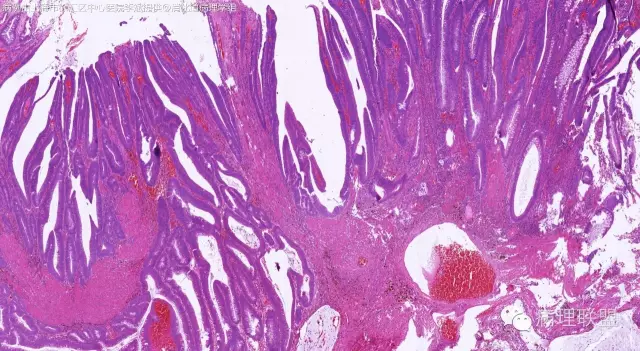

男,64岁,距肛门口45cm息肉大体:灰白结节2*2*1cm(病例由上海市徐汇区中心医院 李斌 提供,致谢!)

管状~绒毛状腺瘤伴低级别上皮内瘤变,黏膜下层部分腺体破裂黏液外溢伴黏液糊形成。

本例部分腺体异位到黏膜下层。

@李斌 李大夫的片子一向漂亮,有赏心悦目的感觉,必须赞一个。这例同意周大夫的意见,低级别绒毛管状腺瘤伴腺体破裂导致的黏液外溢。粘液池周围可见血管扩张淤血、含铁血黄素沉积、肉芽组织形成,提示发生过蒂扭转和出血,这常是造成假浸润、粘液溢出的原因。比较大的绒毛管状腺瘤会有分叶结构,会有比较粗大的平滑肌干,但缺少P-J息肉叶脉样从主干再分支出来的细平滑肌束。作为错构瘤性息肉的一种,P-J息肉的腺体可以分支、扩张、腺腔不规则,但没有细胞异型性,伴发异型增生时,局部出现细胞异型性但不会像这例这样齐刷刷都是异型的腺体。